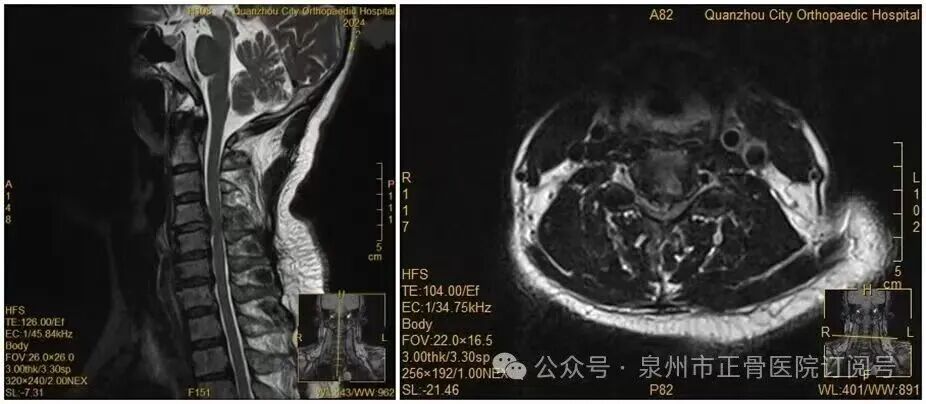

福建省泉州50岁的王女士因反复手麻、酸痛前往泉州市正骨医院就诊,被确诊为颈椎间盘突出症。

医生介绍:“当时检查显示,她的颈椎间盘已经巨大脱出,完全符合手术指征,我们建议她尽快手术干预”。但王女士心存顾虑,坚持选择保守治疗。

图说:王女士术前MRI

没想到,会诊当晚,王女士翻身拿手机的瞬间,双手突然失去知觉——经检查,其关键肌肌力已降至1级或0级,确诊为瘫痪。

医生推测,王女士翻身时脱出的椎间盘突然进一步卡压到脊髓神经,引发了急性症状。